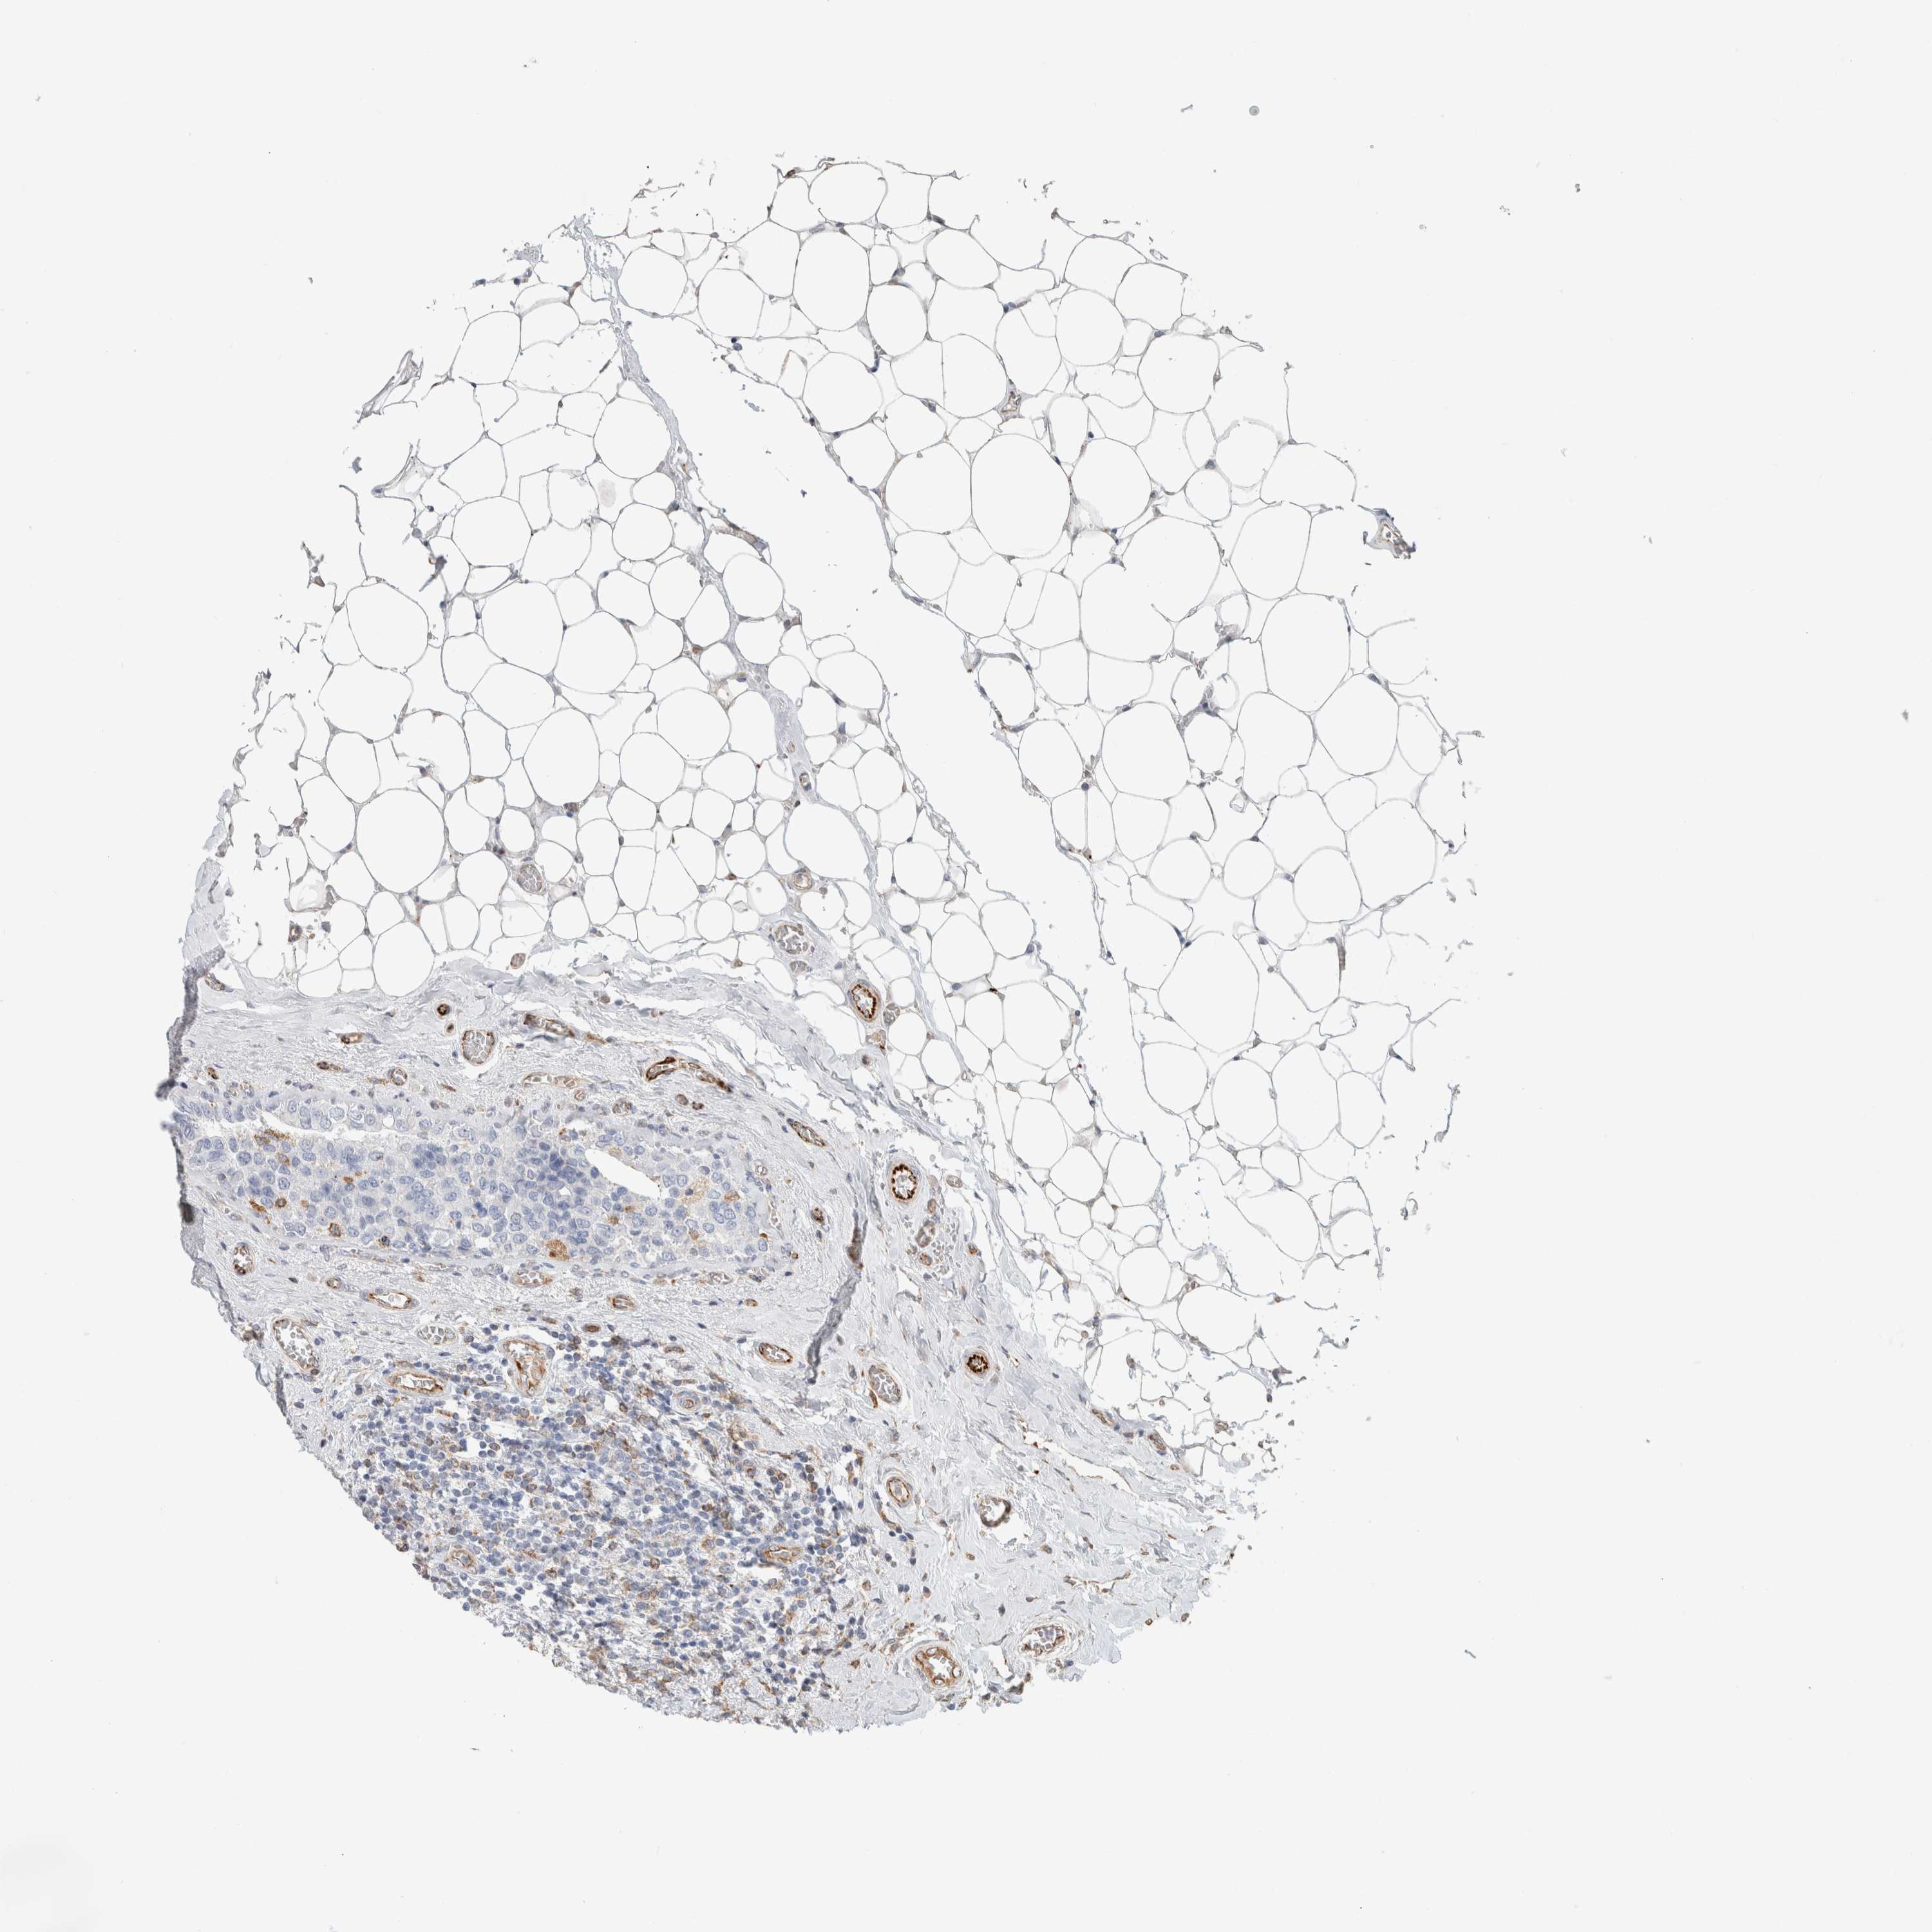

CANCER BREAST CANCER Show tissue menu

BRCA TCGA BRCA VALIDATION PROTEIN EXPRESSION